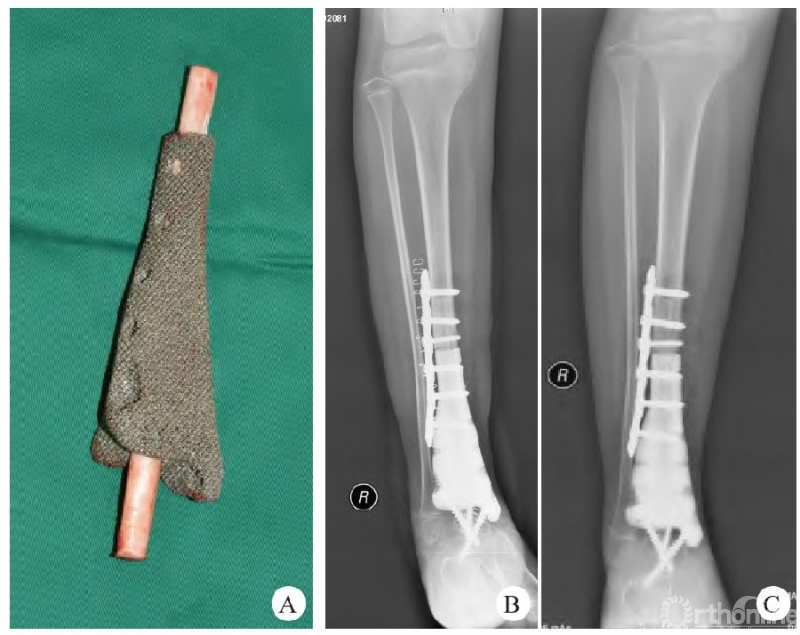

前臂原发恶性骨肿瘤发病率极低,前臂肌群解剖结构复杂且与手的精细运动密切相关,神经血管密布空间狭小。恶性骨肿瘤侵犯周围软组织往往造成重要神经血管受累而保肢困难。对于此部位的保肢手术缺乏足够的治疗和预后证据,而青壮年的上肢截肢势必给个人带来严重残障和家庭负担。

北京积水潭医院骨肿瘤团队,依靠优势的病例资源和长期随访证据,总结了近20年的前臂原发恶性骨肿瘤外科手术切除重建方法,统计分析出预后相关危险因素。为术前评估肿瘤切除安全边界、重建方式优劣提供了科学依据。该研究作为截止目前最大宗的前臂原发恶性骨肿瘤数据,为保肢治疗提供了安全切除评估要点、重建术式选择策略。为此类罕见肿瘤患者治疗提供了重要参考。